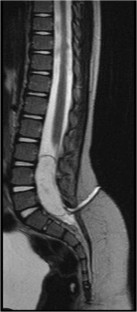

Fig. 1